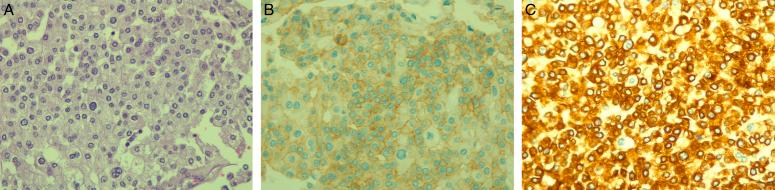

CASE PRESENTATION

The authors report a case of a 51-year-old male patient with renal cell carcinoma. During his evaluation, he seemed to have a lung mass which revealed to be a carcinoid tumour. As the patient had two primary malignancies, he was managed according to the treatment options for each tumour.

病例介绍

作者报告了一例51岁男性肾细胞癌患者。在对他进行评估期间,他似乎有一个肺部肿块,结果显示为类癌肿瘤。由于该患者患有两种原发性恶性肿瘤,因此根据每种肿瘤的治疗方案对他进行了处理。